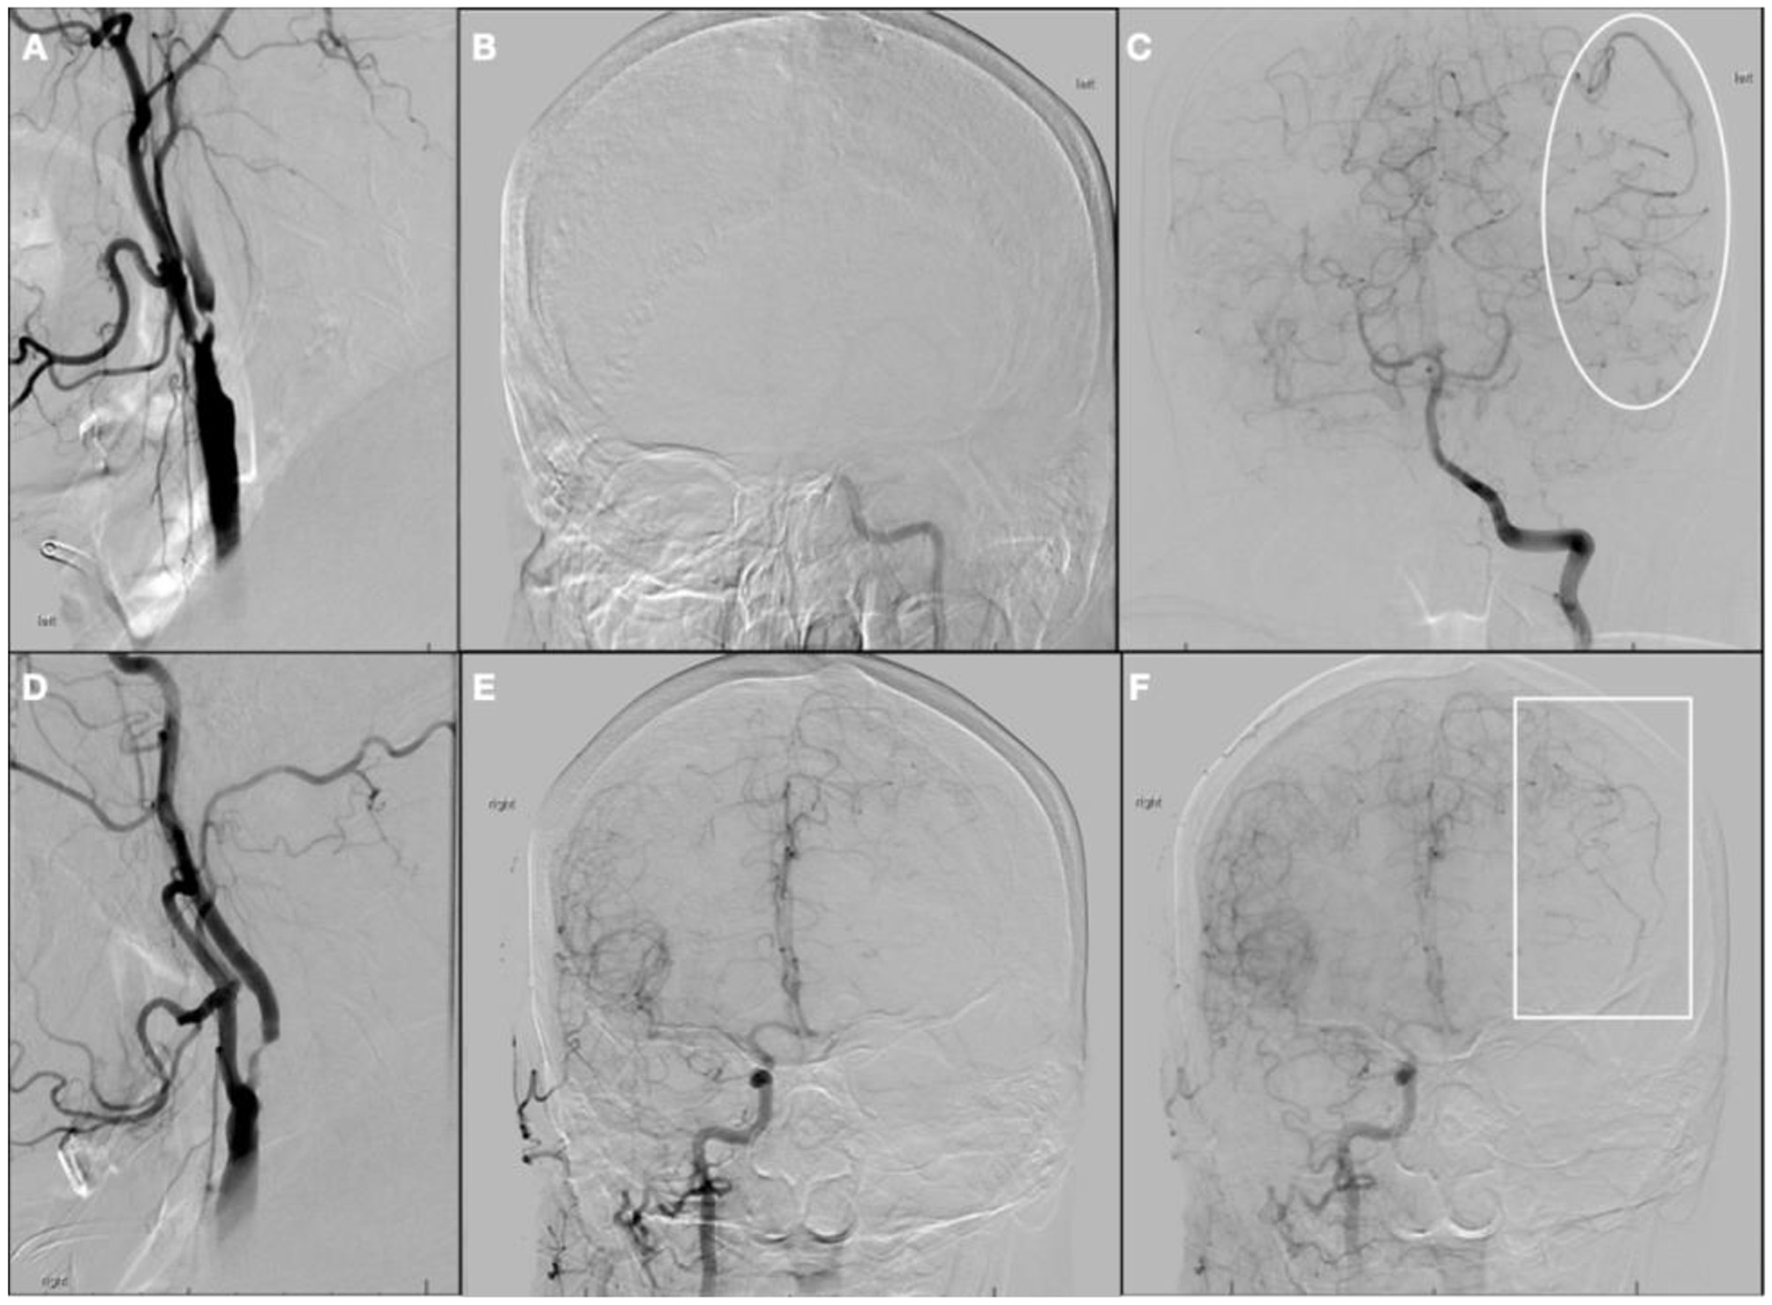

One week later, the patient underwent a repeat diagnostic cerebral angiogram to reevaluate severe bilateral carotid stenosis, which revealed persistent severe cervical left ICA stenosis (Figure 4A) but interval recanalization of the left ICA terminus and associated early hyperemia within left MCA territory (Figures 4B, C). The risks of revascularization of the proximal left ICA, given the risk of hyperperfusion, were discussed with the patient, as well as the potential benefit from contralateral ICA stenting in light of the interhemispheric cross-filling. The decision was made to pursue two-stage stenting, starting with the asymptomatic severe right proximal ICA stenosis, followed by the left ICA. The patient underwent successful right ICA stenting without complications (Figures 4D, E) and had an uneventful overnight ICU stay with no neurological or hemodynamic alterations. A repeat CTP the next day showed no core yet a still large penumbra area at risk (Tmax > 6 s) on the MCA territory, 63cc (Figure 4F). He was discharged that day following the procedure with plans to return to undergo stenting of the left internal carotid.

Figure 4. Digital subtraction angiography 1 week after initial presentation and post-stenting computerized tomography perfusion (CTP). (A) left common carotid artery (CCA) injection, neck lateral view; (B) left CCA injection, head anterior–posterior view showing terminal left internal carotid artery (ICA) recanalization (square); (C) left CCA injection, lateral view showing early hyperemia on left middle cerebral artery (MCA) territory (ellipse); (D) right CCA injection, neck lateral view pre-stenting; (E) right CCA injection, neck lateral view post-stenting; (F) CTP 1 day after right ICA stenting showing no core and penumbra of 63cc on left MCA territory.